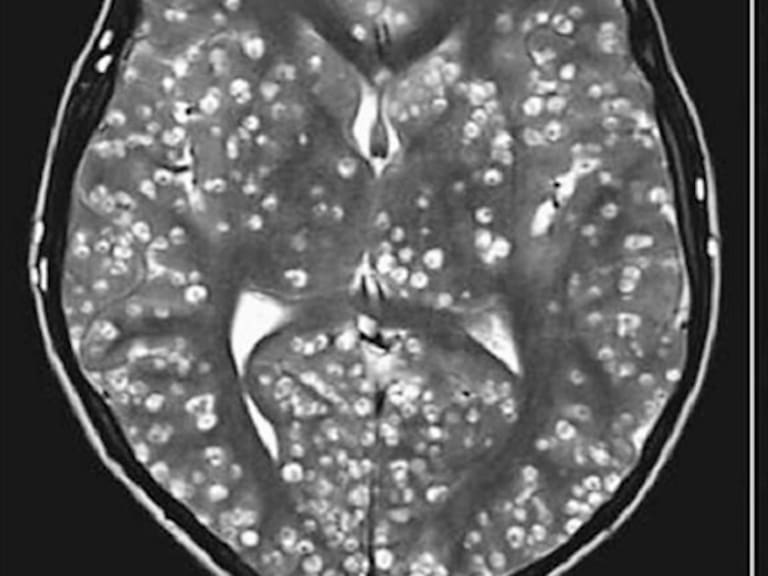

"Tenía miles de quistes. No he visto algo así en toda mi carrera", aseguró el doctor tratante de un joven de 18 años en Faridabad.

El Instituto Médico ESIC de Faridabad recibió a un joven de 18 años con espasmos, dolores de cabeza y malestar constante en su ingle. Los exámenes detectaron inflamación en el ojo izquierdo y una sensibilidad inusual en el testículo derecho. Una resonancia magnética mostró un cerebro plagado de larvas.

El doctor Nishanth Dev explicó al diario Indian Express que "vimos que lo tenía lleno de gusanos. Una ecografía del ojo demostró que estaba infestado. Estudios posteriores revelaron que también los tenía en los testículos". El paciente murió a las semanas a causa de una neurocisticercosis masiva.

"Tenía miles de quistes. No he visto algo así en toda mi carrera", dijo Dev. Por esta razón el médico su colega S. Zafar Abbas publicaron el caso en la New England Journal of Medicine. El hecho ocurrió hace cuatro años, pero la infección expone el problema sanitario ante una enfermedad común en países pobres.